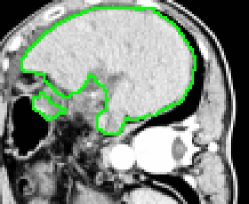

4.1 Metrication artifacts and minimal surfaces

We begin by comparing the CCMF segmentation result with the classical max-flow algorithm (graph cuts). Figure 3 shows the segmentation of a brain, in which the contours obtained by graph cuts are noticeably blocky in the areas of weak gradient, while the contours obtained by both AT-CMF and CCMF are smooth.